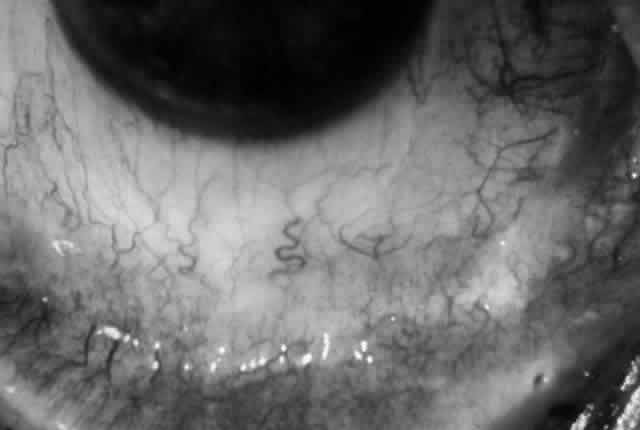

Clinically, the ocular disease in cicatricial pemphigoid (OCP) may present unilaterally in the form of a chronic, recurrent catarrhal conjunctivitis, but it eventually becomes bilateral. Subepithelial fibrosis is characteristic of stage 1 of OCP (Fig. 7). Stage 2 shows fornix foreshortening (Fig. 8), and symblepharon formation is the hallmark of stage 3 (Fig. 9). Stage 4, end-stage disease, is characterized by ankyloblepharon and surface keratinization (Fig. 10). Obstruction of the lacrimal ductules and meibomian gland ducts eventually produces an unstable tear film and progressive sicca syndrome, but it is to be emphasized that OCP is not a dry-eye syndrome until late in the disease course.20 Trichiasis and entropion occur because of the subepithelial fibrosis, with eventual keratopathy, corneal neovascularization, and corneal ulceration and scarring.20

Fig. 7. Stage 1 cicatricial pemphigoid, with cicatrizing conjunctivitis, and fine striae-type areas of subepithelial fibrosis, but without evidence of shrinkage of the conjunctiva.

Fig. 8. Stage 2 cicatricial pemphigoid, with fornix foreshortening and subepithelial fibrosis without frank symblepharon formation.

Fig. 9. Stage 3 of an eye affected by cicatricial pemphigoid. The conjunctival “shrinkage” continued and a frank symblepharon developed.

Fig. 10. Stage 4 cicatricial pemphigoid. Progressive shrinkage of the conjunctiva resulted in extreme trichiasis and distichiasis and keratopathy, with compromise of meibomian ductules and lacrimal ductules and the production of a totally dry eye.